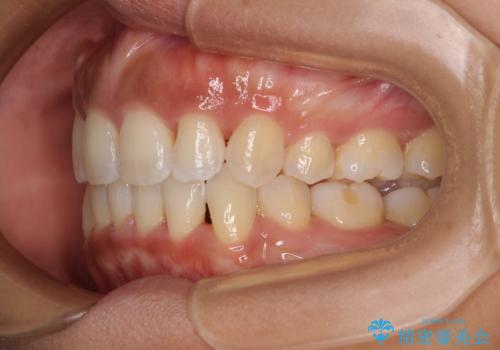

- 下唇が突き出るような口元の突出感が気になるとのことで来院された患者様です。

上下顎ともに前突した歯列であったので、上下ともに左右の第1小臼歯4本を抜歯し、ワイヤー装置にて矯正治療を行うこととしました。

抜歯スペースに前歯を移動させることで歯の突出感が改善され、非常に唇が閉じやすい仕上がりとなりました。